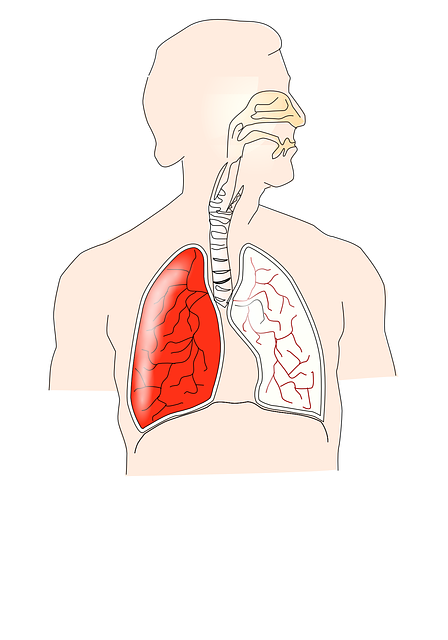

폐암의 경우 초기에는 증상이 없는 경우가 흔히 있으며 통증도 증상도 없이 생활하다가 건강검진을 통해 발견하는 경우도 생각보다 흔합니다. 폐암 증상은 기침 흉통 목소리의 변화 체중감소 호흡곤란 각혈 같은 증상을 보입니다. 오늘은 폐암 초기증에 대해서 알아보겠습니다.

폐암 초기 증상

폐암은 폐에 악성종양 암세포가 증식하여 덩어리를 형성해 폐기능의 문제가 생기게 하는 질환으로 진행이 심할 경우 다른 장기로 전이되기도 합니다. 진행 정도가 심하지 않은 경우 수술적 치료와 약물치료를 통해 증상을 완화할 수 있는 질병으로 알려져 있습니다. 폐암 초기에는 수술로 완치가 가능하며 예후도 좋은 편이지만 1~4기까지의 진행 정도에 따라서 사망률이 높아지는 질환입니다.